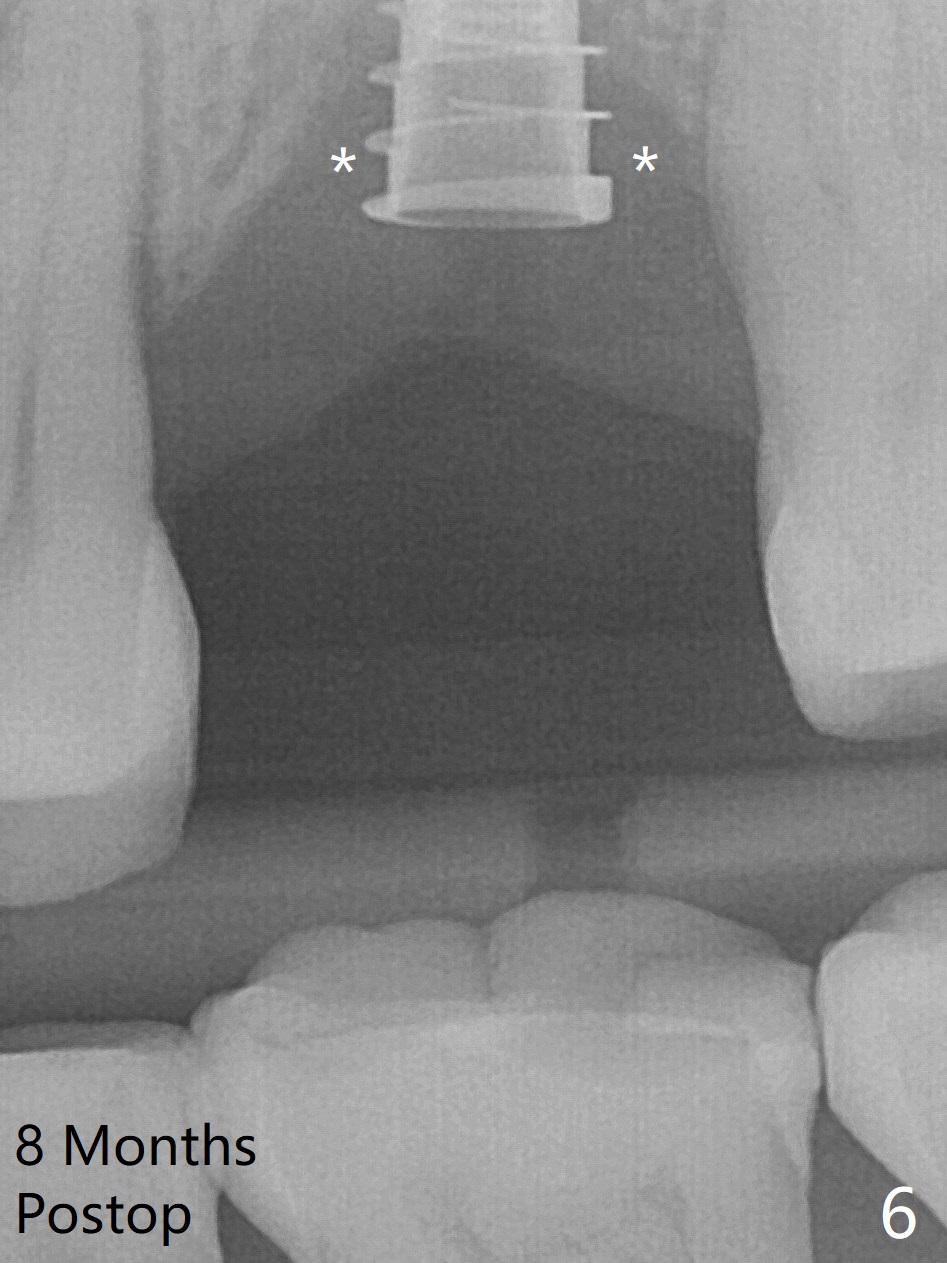

Preop exam shows the narrow ridge at #14. Magic split is used for access and initiation of osteotomy and bone expansion, followed by 3 mm Magic Expander for 11 mm (ME, Fig.1 (yellow line: sinus floor)). In fact the bone is soft. After use of 3.8 mm ME and Lindamann bur (to move the osteotomy distobuccally), a 4x11 mm dummy implant is placed with 20 Ncm (Fig.2). Following use of Lindamann bur for the same purpose as mentioned above, a 4.5x9 mm IBS implant is placed 3 mm subgingival with <30 Ncm (Fig.3,4). Bone graft is placed for sinus lift prior to implantation. A 5x3 mm healing abutment is placed. Bone loss is minimal 3.5 months postop (Fig.5) and striking 8 months postop (after crown cementation, Fig.6-8). The bone loss persists in spite of crown and abutment removal (Fig.9,10). Bone graft or implant redo is planned.